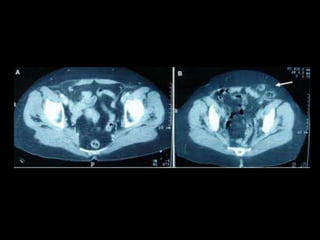

• TAC: Permite identificar los músculos que constituyen

la pared abdominal anterior y el transverso del

abdomen, así como el contenido del saco herniario

Métodos diagnósticos

• En pacientes muy obesos y con sacos herniarios

muy pequeños.

• USG dinámico, en reposo y con maniobra de

valsalva

• TAC dinámica